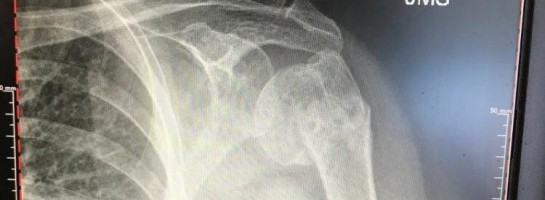

I created 3 websites and was making some good progress. Then, in May of last year, I fell while on vacation with my sister, Kirsten, in Puerto Vallarta, Mexico and broke my Humerus Bone in two with several fractures around my left arm and mostly in my shoulder. You can see in the picture where it is disconnected from my shoulder!

I got top notch care and made some great friends! They reset my arm---OUCH!---took x-rays and set my left arm in a sling.